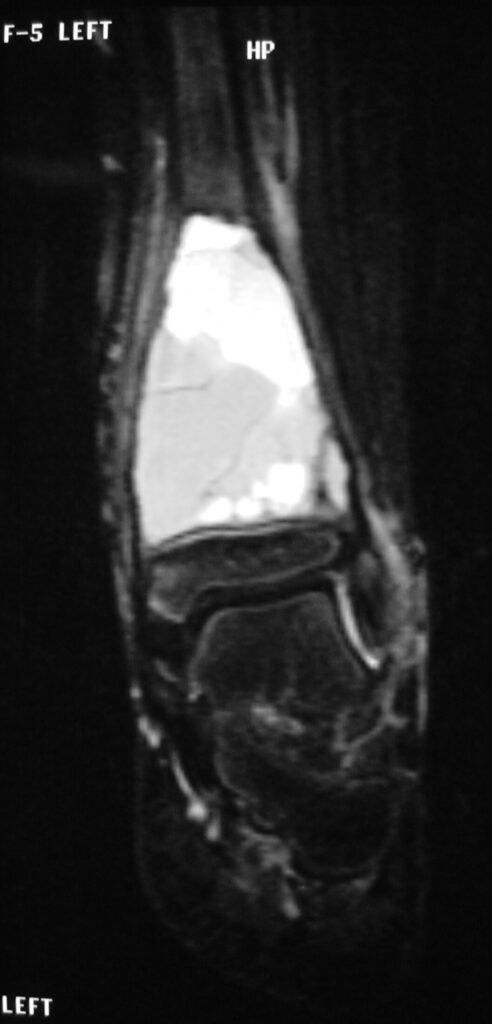

MRI

- Geographic well circumscribed

- High signal on T2 weighted MRI images

- Fluid/Fluid level (T2) are highly characteristic

Fig 2 a-e. MRI of an ABC of Distal Tibia: Fig 2 a-c: geographic cystic expansile lesion with fluid-fluid levels. The fluid-fluid levels are caused by bleeding into the cavities. The blood collects and the degredation products settle to the gravity dependent areas of the cavities. This shows up as fluid-fluid levels on the MRI. Fig 2 d,e: This is a gadolinium enhanced MRI of the ABC of the distal tibia. There is peripheral and septal enhancement indication cyst formation. The contrast outlines the cystic cavities but does not enter into the center

Fig 2 a: Coronal T2 weighted MRI of an ABC

Fig 2b: Sagittal T2 weighted MRI of and ABC

Fig 2c: Axial T2 weighted MRI of an ABC

Fig 2d: Coronal gadolinium enhanced MRI of an ABC

Fig 2e: Sagittal gadolinium enhanced MRI of an ABC